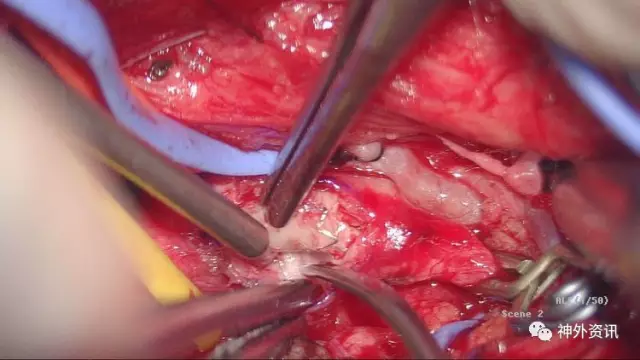

这是剥离支架后的外中膜

显微镜下7-0缝线缝合切口,松开阻断夹,VA管腔充盈好,无活动渗血,手术很顺利

这是切下的标本,切开后见支架被增生内膜包裹,内腔消失